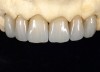

Fig 12. Posterior monolithic high-translucent zirconia onlay and crown restorations.

Figure 12

A 40-year-old patient presented with the chief complaint: “My teeth are cracking, and I would like to have my original bite.” Dental findings included Class I occlusion with slight misalignment between teeth Nos. 8 and 9. Generalized severe occlusal wear and slight Class I mobility of teeth Nos. 23 to 26 were noted. Caries lesions were found on teeth Nos. 2, 4, 6, 8, 9, and 14 and abfraction lesions on teeth Nos. 4, 5, 10, 11, 13, 20, and 21. Figure 1 through Figure 3 depict the preoperative situation. Full-mouth rehabilitation was suggested. The goals for the restorative treatment were management of erosive etiology, conservation of tooth structure, and long-term protection of the restorations. A diagnostic wax-up was instrumental in determining functional and esthetic treatment goals and establishing new anterior guidance (Figure 4). A comprehensive, step-by-step treatment approach was applied, which, after periodontal pretreatment, caries control, and provisionalization, included definitive preparation (Figure 5) and restoration of the maxillary anterior teeth to establish anterior occlusal guidance. CAD/CAM–fabricated full-contour monolithic high-translucent zirconia crowns (Katana™ UTML Ultra Translucent Multi-Layered, Kuraray Noritake Dental, kuraraynoritake.com) were fabricated (Figure 6 and Figure 7) and cemented with self-adhesive resin cement (Panavia SA, Kuraray Noritake Dental). Figure 8 demonstrates the cemented anterior crowns and refined conservative preparations of posterior teeth, which were performed with minimal tooth-structure removal. High-translucent monolithic zirconia onlays and crowns were fabricated (Katana Zirconia UT, Kuraray Noritake Dental) (Figure 9 to Figure 12). The posterior restorations were adhesively bonded following the APC zirconia-bonding concept. APC-Step A involved air-particle abrasion with 50-μm aluminum oxide at 1.5 bar with a chairside microetcher (Figure 13), followed by application (APC-Step P, Figure 14) of a special ceramic primer (ClearfilTM Ceramic Primer, Kuraray Noritake) with adhesive phosophate monomers (MDP). Relative moisture and contamination control was achieved with cotton rolls and retraction cords. Rubber dam placement, which is always preferred, was difficult in this situation. The enamel surfaces of the abutment teeth were selectively etched (Figure 15) with 35% phosphoric acid (K-Etchant Gel, Kuraray Noritake Dental) and the dentin conditioned (Figure 16) with a self-etch dentin primer (Panavia V5 Tooth Primer, Kuraray Noritake Dental). A dual-cure adhesive resin (Panavia V5 Paste Universal, Kuraray Noritake Dental) was dispensed directly into the restorations with an automix syringe. The restorations were inserted, and excess cement was carefully removed (Figure 17 and Figure 18) before light polymerization (Figure 19). Postoperative views depict the treatment outcome (Figure 20 to Figure 22).